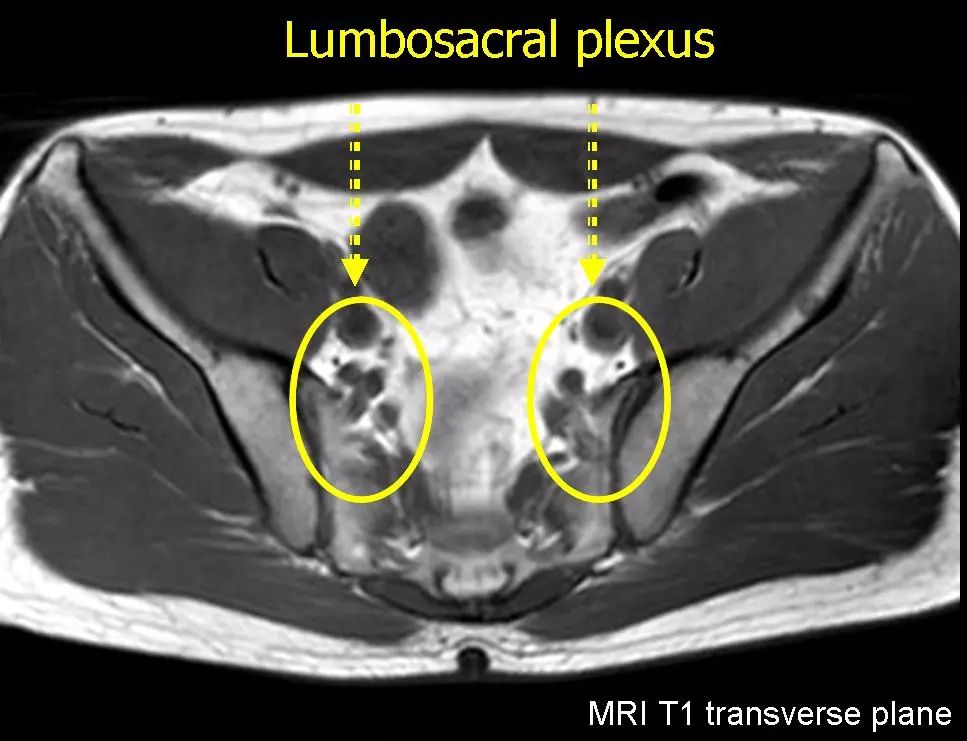

腰骶丛磁共振神经成像(mr neurography of the lumbosacral plexus)

读书笔记丨腰骶丛磁共振神经成像(mr neurography of